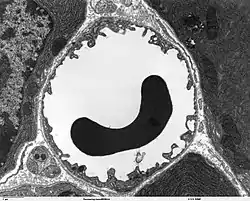

Transmission electron microscope image of a capillary with a red blood cell within the pancreas. The capillary lining consists of long, thin endothelial cells, connected by tight junctions.